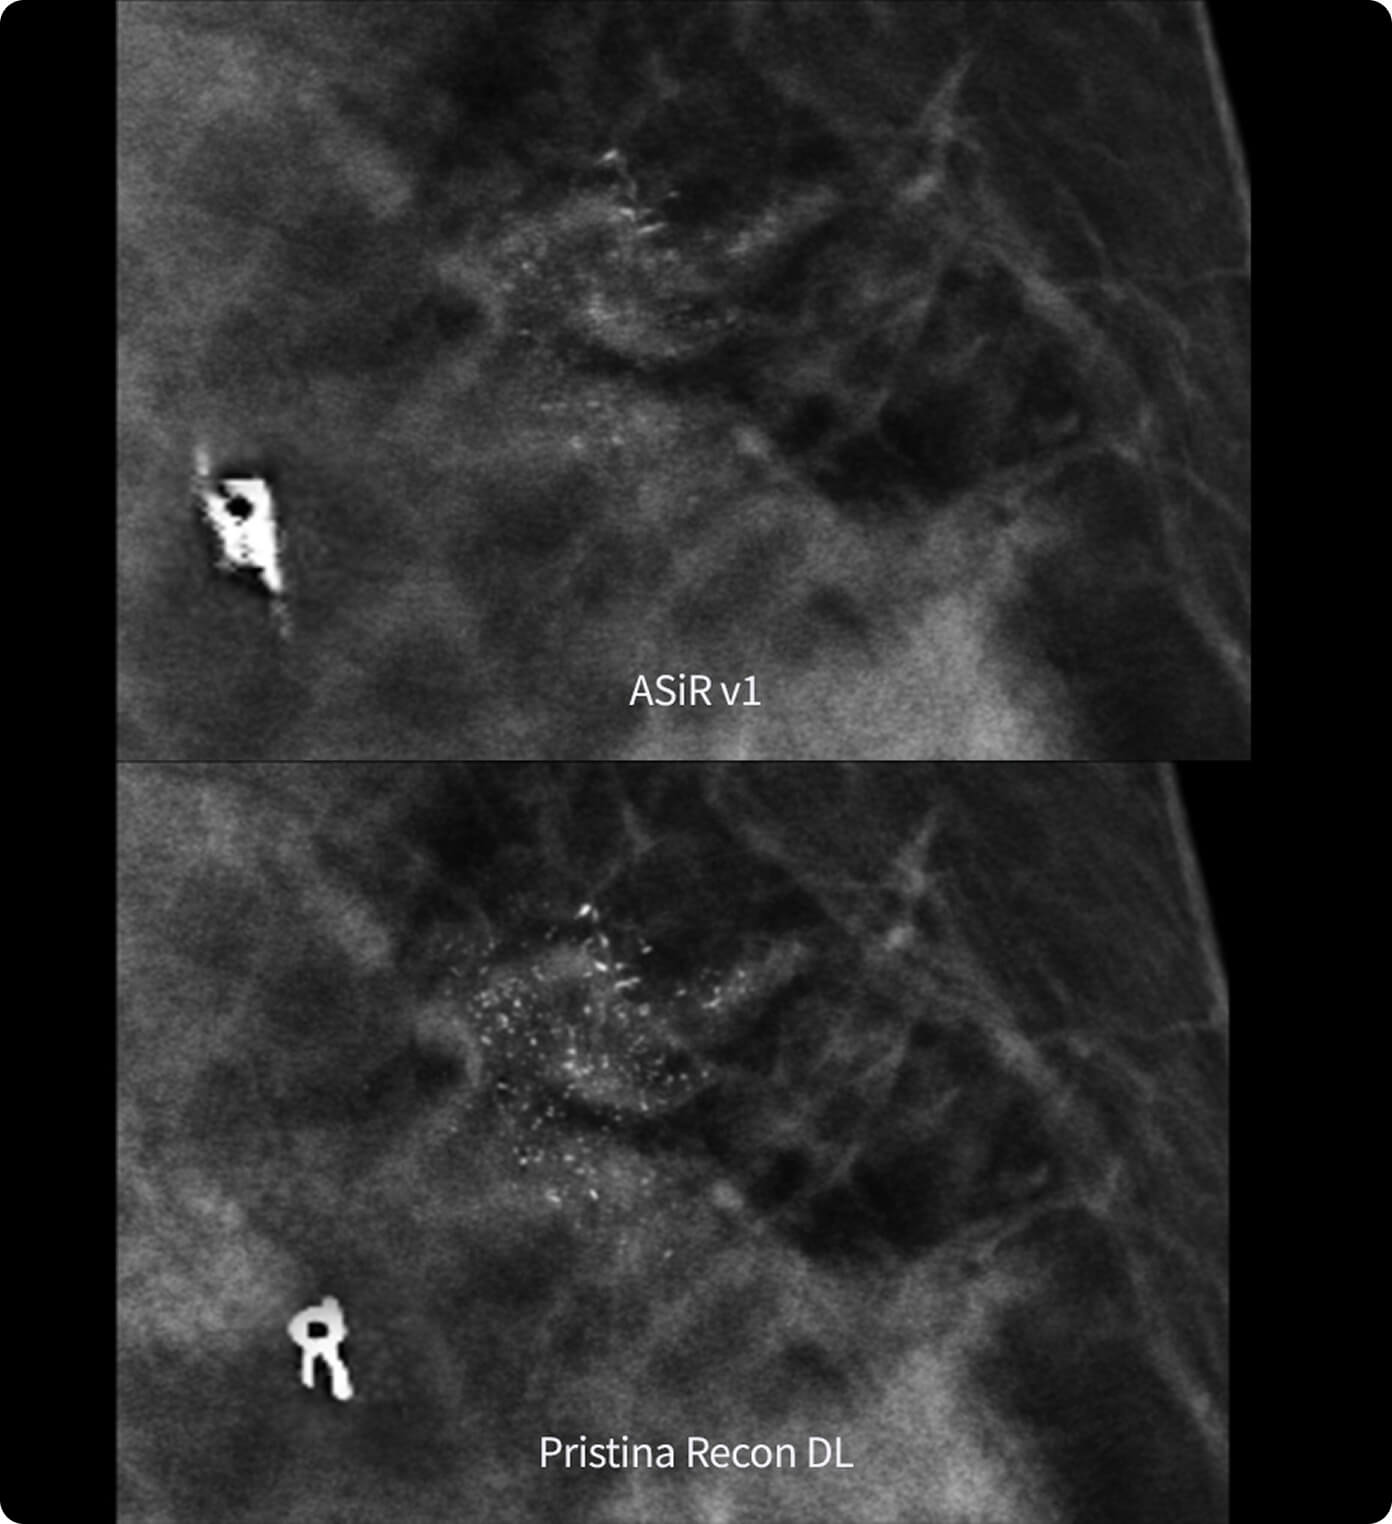

• Une qualité d'image exceptionnelle rendue possible par une largeur d'impulsion réduite et une puissance de crête inégalée pour la production des rayons X.

• Des détails impressionnants grâce à une large gamme de foyers proposés pour les modes d'acquisition scopie et ciné.

Unique set of capabilities to enhance system performance all along the image chain and optimize image quality and dose in real time automatically.